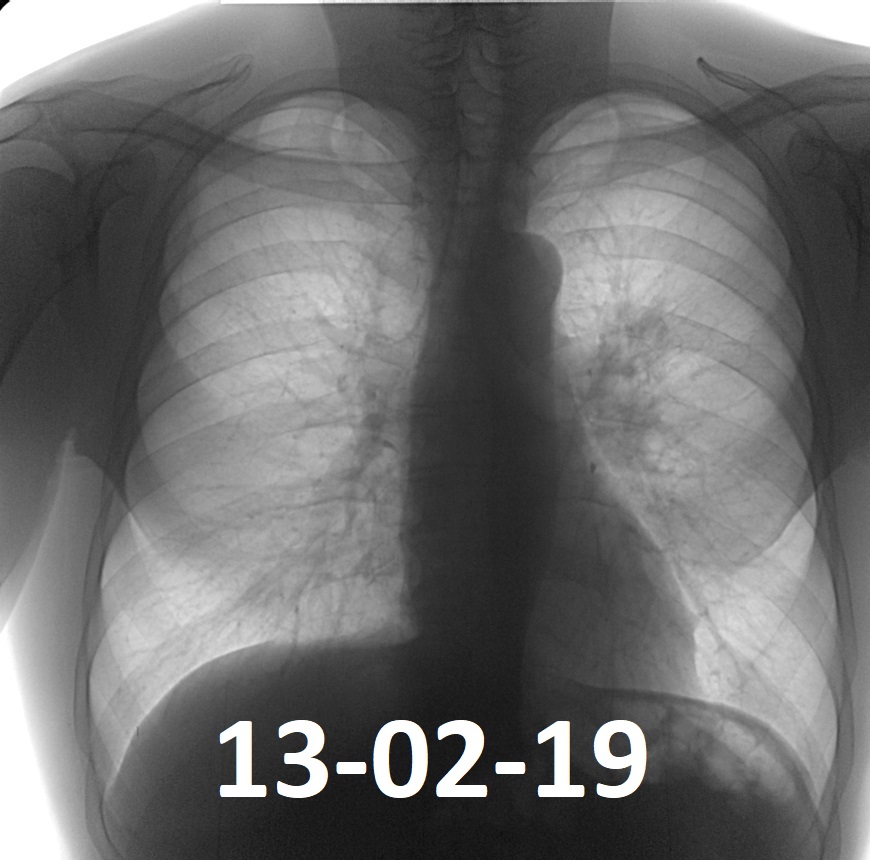

Фотографии рентгеновских снимков без необходимости направления от врача